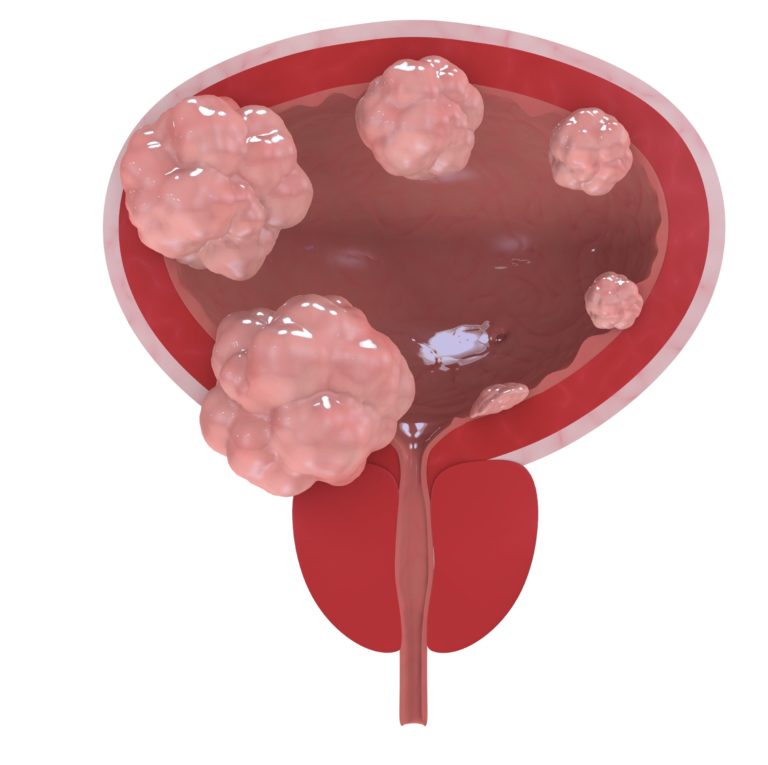

Illustration of different pathological stages of bladder cancer. Stage …

Understanding the Different Types and Forms of Bladder Cancer

Bladder Cancer: Symptoms and Treatment – Healthsoul

Urinary Bladder Tumour Surgery is done for these SYMPTOMS – Cancerclinix

Bladder Cancer

Bladder Cancer | Center for Urologic Care of Berks County

Bladder cancer – Cancer Council Victoria

Bladder Cancer

Bladder Cancer. Signs, Symptoms and Treatment of Bladder Cancer